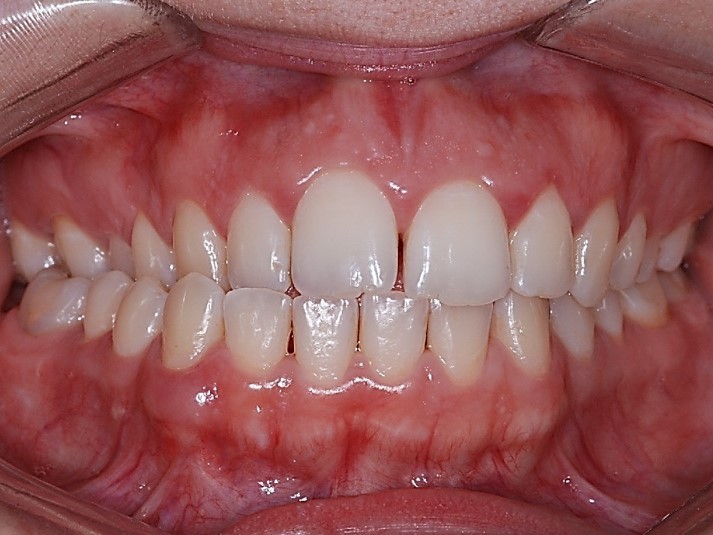

Classe III, articulé postérieur, arcades étroites, arcades asymétriques, déviation de la ligne médiane mandibulaire, décalage de la ligne médiane, rotations, espacement

- Relation de classe I obtenue

- Guidage fonctionnel des canines des deux côtés

- Articulé antérieur corrigé

- Articulé postérieur corrigé

- Surplomb et recouvrement normaux obtenus

- Lignes médianes coïncidentes

- Alignement des deux arcades par dérotation

- Forme de l'arcade améliorée

État initial

État final